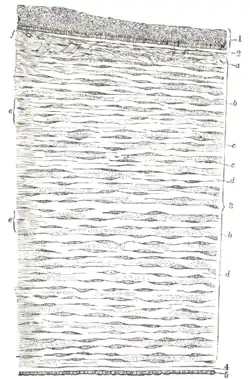

Vertical section of human cornea from near the margin. (Waldeyer.) Magnified.